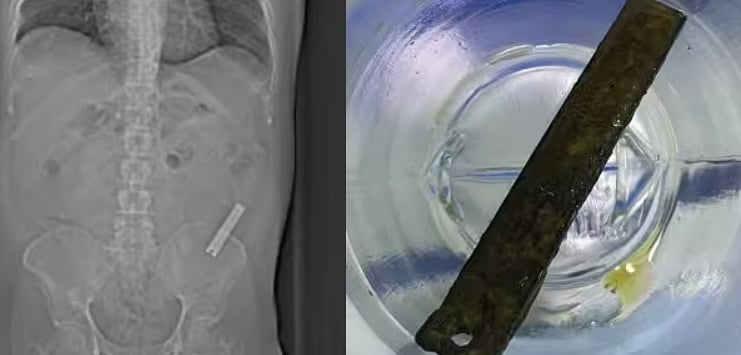

`திட்டுவாங்கன்னு வெளியே சொல்லல'- 8 வருடங்களாக இளைஞர் வயிற்றிலிருந்த நகவெட்டி; மிரண்ட மருத்துவர்கள்! 🕑 Wed, 23 Aug 2023

`திட்டுவாங்கன்னு வெளியே சொல்லல'- 8 வருடங்களாக இளைஞர் வயிற்றிலிருந்த நகவெட்டி; மிரண்ட மருத்துவர்கள்!

பெங்களூருவில், 8 வருடங்களாக இளைஞரின் வயிற்றில் இருந்த நகவெட்டியை லேப்ராஸ்கோப்பி சிகிச்சை (Laproscopy) மூலமாக மருத்துவர்கள் அகற்றியுள்ளனர். வயிற்றுவலி என